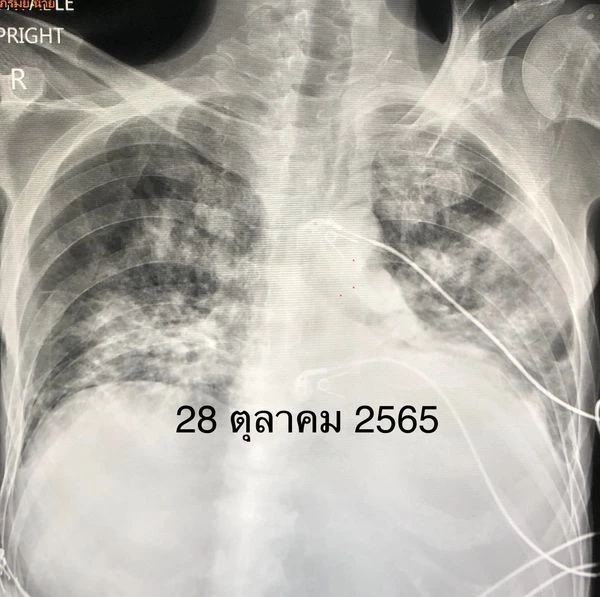

ผู้ป่วยชายอายุ 53 ปี เป็นมะเร็งเม็ดเลือดขาว 3 ปี ฉีดวัคซีนป้องกันโรคโควิด แอสตร้าเซเนกา 2 เข็ม และไฟเซอร์ 1 เข็ม เริ่มมีไข้สูง ไอ เจ็บคอ 3 วัน ตรวจ ATK ให้ผลบวก เหนื่อยมาก เข้าโรงพยาบาลวันที่ 28 ตุลาคม 2565 ระดับออกซิเจนที่ปลายนิ้วต่ำมาก 80% เอกซเรย์ปอดมีฝ้าขาวทั้ง 2 ข้าง (ดูรูป) ตรวจรหัสพันธุกรรม 22 สายพันธุ์ พบไวรัสโควิด RT-PCR SARS-CoV-2 CT value 17.1 ไม่พบไวรัสตัวอื่น เข้าห้องไอซียู ให้ออกซิเจนชนิด high-flow nasal cannula (HFNC) ให้ยาเรมเดซิเวียร์ และยาสเตียรอยด์ชนิดฉีดเข้าเส้นเลือดดำ

คนไข้ไม่ดีขึ้น เหนื่อยมากขึ้น เอกซเรย์ปอดแย่ลง (ดูรูป) ต้องใส่ท่อหายใจ และเครื่องช่วยหายใจ ความดันต่ำจนช็อก ในวันที่ 30 ต.ค. 2565 ต้องให้ยาเพิ่มความดัน